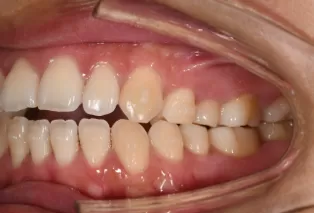

Intraoral photos